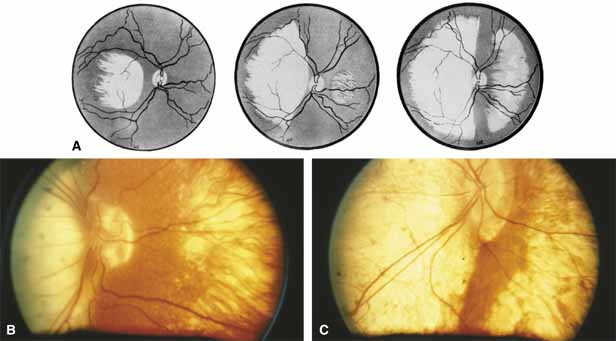

First described by Nettleship12 in 1884, central areolar choroidal dystrophy (CACD) (MIM No. 215500, Phenotype catalog number (MIM) from McKusick VA: Mendelian Inheritance in Man. Catalogs of Human Genes and Genetic Disorders. 12th ed. Baltimore: Johns Hopkins University Press, 1998 [http://www.ncbi.nlm.nih.gov/Omim/]), as it is most appropriately called,13 has been described under many names, including central areolar choroidal sclerosis, central areolar choroidal atrophy, central angiosclerosis, and central senile choroiditis.14,15 The disorder can be autosomal dominant or autosomal recessive, and phenocopies can occur from many other diseases, including mutations of peripherin/RDS16–19 and advanced stages of macular dystrophies (see later text). A locus for CACD has been identified on chromosome 17p.20 The earliest symptoms result from pericentral scotomas and include difficulty reading, poor dark adaptation, reduced visual acuity, and glare sensitivity. The earliest fundus findings are subtle and include pigment epithelial and choriocapillaris lesions in the macula (Fig. 1A) that enlarge and eventually form the punched-out central atrophic lesions typical of this disease (Fig. 1B). Histopathology shows fibrotic scarring with absence of choriocapillaris, retinal pigment epithelium, and overlying photoreceptors in the affected areas.21 The Ganzfeld electroretinogram is usually normal early in the course but may become mildly to moderately abnormal for cone and rod responses late in the course of disease when extensive atrophy of the choroid and secondarily the pigment epithelium and neurosensory retina occurs. Recent studies using the multifocal ERG have indicated that the abnormality of retinal function extends beyond the borders of the visible atrophy and is consistent with presynaptic photoreceptor dysfunction.22 The EOG can be normal or mildly abnormal depending on the extent of associated retinal pigment epithelial dysfunction.

Other forms of central choroidal dystrophy exist that do not show the discrete oval lesions of typical central areolar choroidal sclerosis. These forms of central choroidal choriocapillaris atrophy often present with progressive pigment epithelial mottling and patchy choriocapillaris atrophy initially limited to the macula (Figs. 2A and 2B). With time, the atrophy enlarges and eventually encompasses the entire posterior pole (Fig. 2C). For this form of central choroidal atrophy, a gradual transition usually occurs from atrophic central pigment epithelium and choriocapillaris to essentially normal retina and choroid in the peripheral fundus.